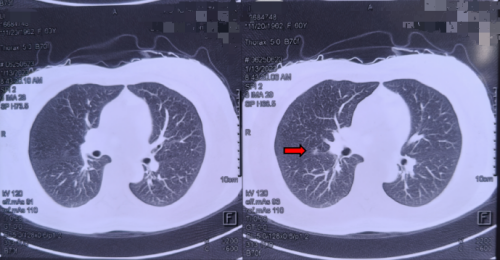

49岁的患者李女士,2023年1月体检发现右肺中叶有一处10mm的磨玻璃结节(GGO),影像提示“AIS可能”(原位癌不排除)。她辗转多家医院,均被告知“定期观察”,但内心始终焦虑不安。后经人介绍,于7月来到鼓楼中医医院结节专病门诊就诊。

患者首次于2023-01-13外院肺CT影像图(3im29)